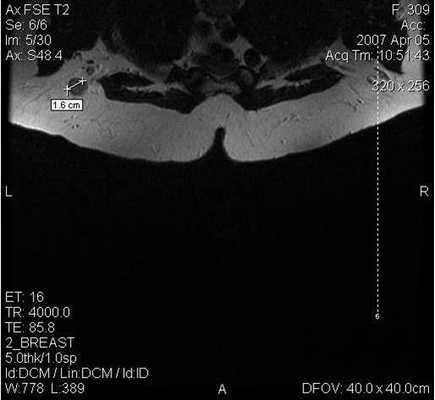

Магнитно-резонансная томография

Поскольку традиционный маммографический скрининг у женщин до 40 лет малоэффективен, для скрининга может понадобиться альтернативная методика — МРТ. Современная контрастная магнитно-резонансная томография — высокочувствительный метод диагностики заболеваний молочной железы.

МРТ-диагностика рака молочной железы

У женщин с мутациями BRCA1 или BRCA2 при проведении МРТ возможно диагностировать рак молочной железы на самых ранних стадиях.